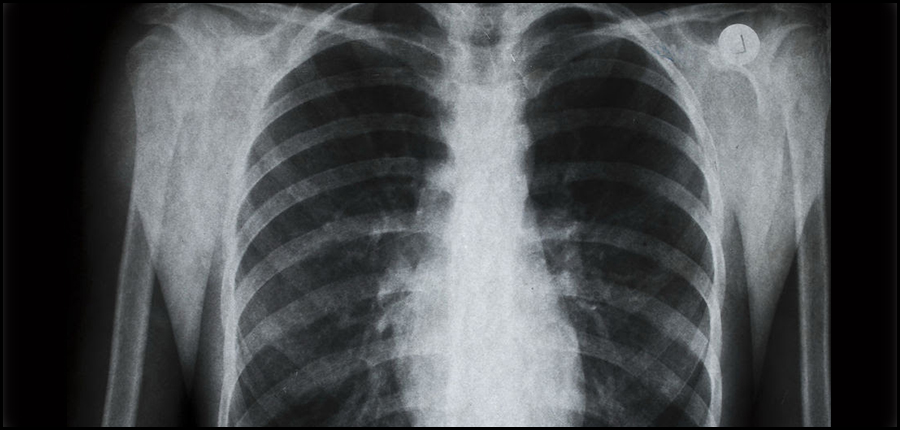

Stopper la progression du cancer agressif du poumon

Une nouvelle thérapie ciblée arrête pendant plus de deux ans la progression d'une forme agressive du cancer du poumon, soit près de trois fois plus longtemps que le traitement de référence actuel, selon les résultats d'un essai clinique.

l'alectinib, a ainsi bloqué 15 mois de plus la prolifération de ce cancer pulmonaire non à petites cellules (CPNPC) avec la mutation génétique ALK, que le Xalkori (crizotinib) du concurrent américain Pfizer, montrent les données de cette étude menée avec 303 patients.